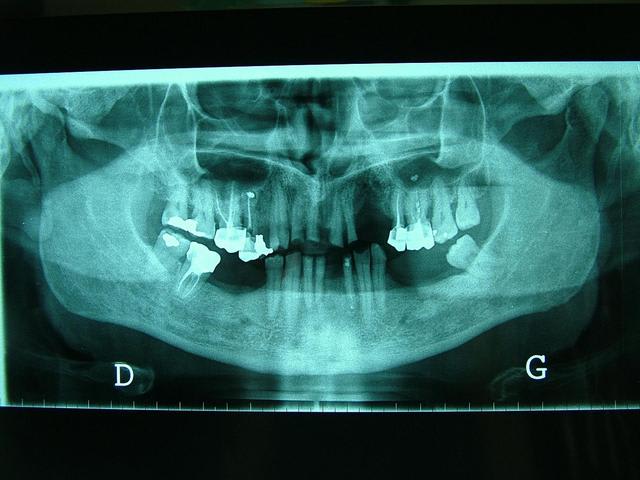

faut voir comment sont ses dents residuelles,mobiles ou pas,il y a un grand manque osseux d'un (coté droit écran,je ne sais dans quel sens tu as mis la pano )extraction recente?

Pano correspond aux modèles ????

C'est le jeux des 7 erreurs ? ou je te prends pour un Mickey ?

Pano inversée

Oui...egressé et usée. Regarde l'os alveolaire de la pano.

Regarde aussi le collet de la 43 et 46...

Je ne vois pas quel problème il y a avec la pano?

Je confirme il y a un calage posterieur...presque pas de perte de DV. Donc la distance "maxillo-mandibulaire" n'a pas diminuée.

Il est vrai que la DV me semble conservé car il y a un calage postérieur côté droit et côté gauche.